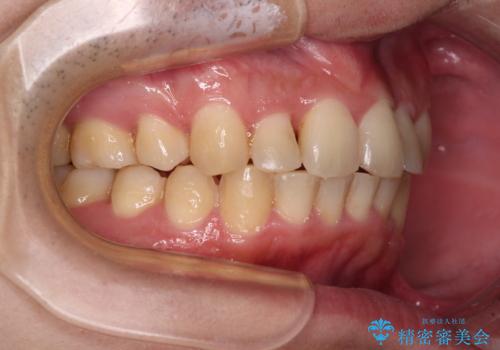

強い咬み込みですり減った前歯 デコボコを抜歯矯正で整える

口元の突出感はないものの、上顎前歯のデコボコが著しかったため、上顎左右第一小臼歯2本を抜歯することとしました。

咬合力が非常に強く、抜歯したスペースがなかなか閉じないであろうことは予想できましたが、思っていた以上に期間がかかりました。

前歯のすり減りも著しかったため、仕上げの位置の調整にも期間を要しました。